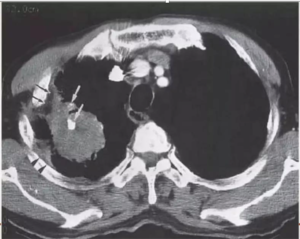

10-year-old child with tuberculosis, shows widening of the right paratracheal stripe

CECT show tuberculous nodes that show central areas of low attenuation suggestive of caseous necrosis and peripheral rim enhancement.

TUBERCULOUS NODE